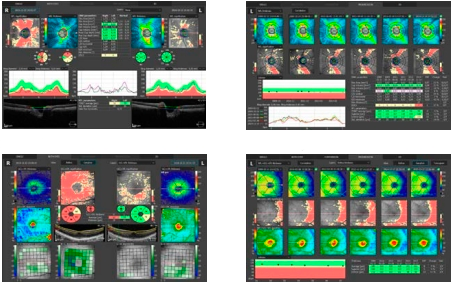

Глаукома

Различные средства для исследования глаукомы, для анализа количественных характеристик слоя нервных волокон, ганглиозных клеток и вершины оптического нерва с составлением шкалы возможности дефекта диска дают возможность максимально точно провести анализ и слежение за течением глаукомы во времени.

Cетчатка

Одно отсканированное изображение макулы в 3D позволяет провести диагностику сетчатки и глаукомы. ПО в автоматическом режиме различает 8 слоев сетчатки, это необходимо для качественного исследования и формирования диаграммы изменений в здоровье больного человека. Наличие совершенно разных методик обработки результатов и презентации дает возможность отдать предпочтение наиболее действенной для пациента, увеличивая эффективность работы.